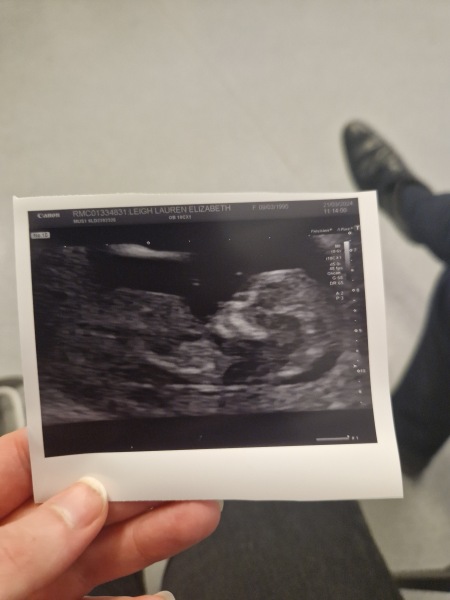

Just back from our second and last scan at our fertility clinic and the baby was really moving lots! We are 9 weeks tomorrow and baby was measuring bang on 8+6!

OCTOBER 2024 BABIES :) THREAD 3

@Btowngirl wow look at your beautiful baby!! Xx